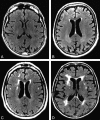

Background and purpose: White matter hyperintensities (WMHs) are frequently characterized as markers of cerebrovascular disease, whereas medial temporal atrophy (MTA) is a recognized marker of Alzheimer disease (AD). Our purpose was to test the reliability of a visual rating system (VRS) in evaluating WMHs and MTA and in distinguishing healthy from cognitively impaired subjects.

Materials and methods: Subjects (n = 192) enrolled in the Florida Alzheimer's Disease Research Center were diagnosed with no cognitive impairment, nonamnestic mild cognitive impairment (na-MCI), amnestic MCI (a-MCI), or probable AD. The severity of WMHs was assessed on T2-weighted fluid-attenuated inversion recovery axial MR images, and the severity of MTA was evaluated on 1.5-mm-thick coronal MR images by using a computer-based visual rating system. Cardiovascular risk factor scores were calculated as the sum of 10 independent cardiovascular risk factors.